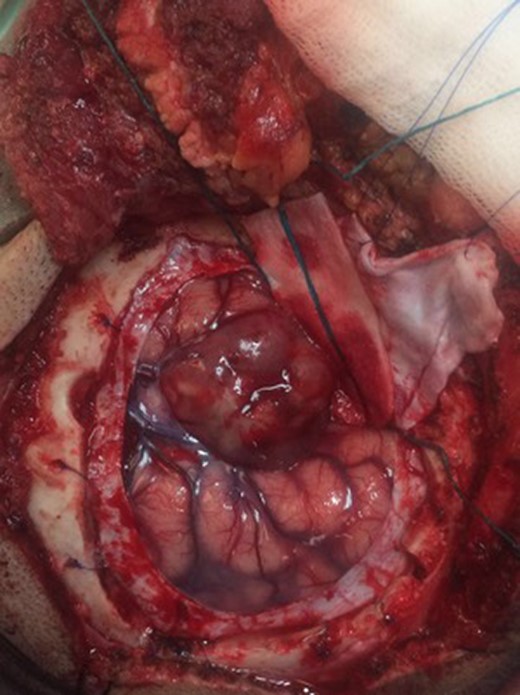

A classic pterional approach was performed, we found a multilobulated and vascularized mass with exophytic component at the level of the left Sylvian fissure (Fig. 2). A macroscopic total resection was performed, with abundant hemorrhage (900 mL). At the follow up the next month, she got 90 points in the Karnofsky scale.

Macroscopic image of the tumor. Exophytic growth can be seen with the involvement of the arachnoid plane at the level of the Sylvian fissure.